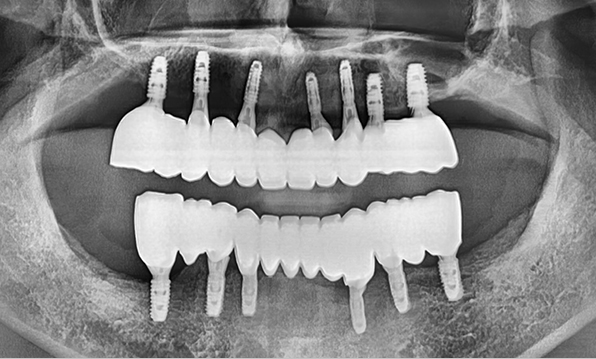

Before After

Case 04